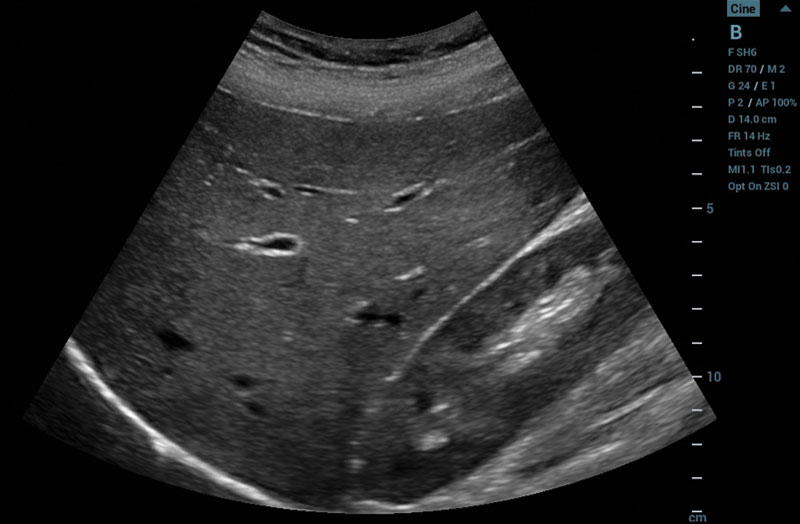

The ZS3 Ultrasound System Diamond Edition 2.0 is the ultimate imaging platform combining premium performance and mobility for today’s demanding ultrasound environments. Equipped with next generation ZONE Sonography® Technology+ (ZST+), the ZS3 System takes image clarity to new heights across a broad spectrum of body types from pediatric to bariatric. With every pixel in focus to imaging depths up to 40cm, the ZS3 System delivers unsurpassed image quality for the widest range of clinical applications.

The ZS3 Radiology Ultrasound System is a smaller, lightweight system that glides into place. An extended battery combined with rapid transition times results in increased exam efficiency and patient throughput.